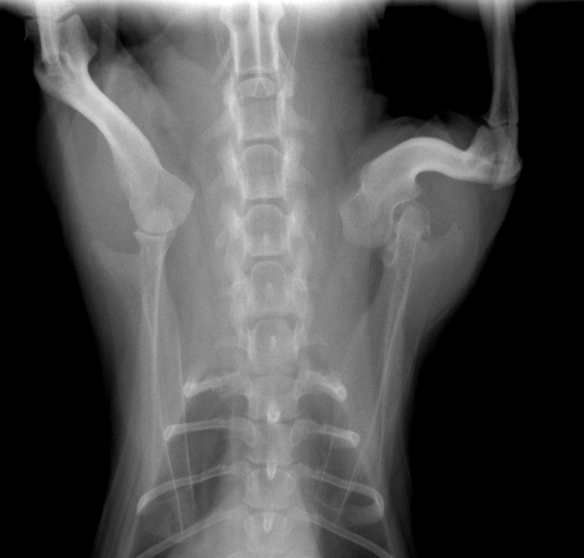

Ct検査vol 25 日曜診療を行っている動物病院なら福岡市の香椎ペットクリニック

Ctスキャンによる犬の肩の解剖図 Vet Anatomy